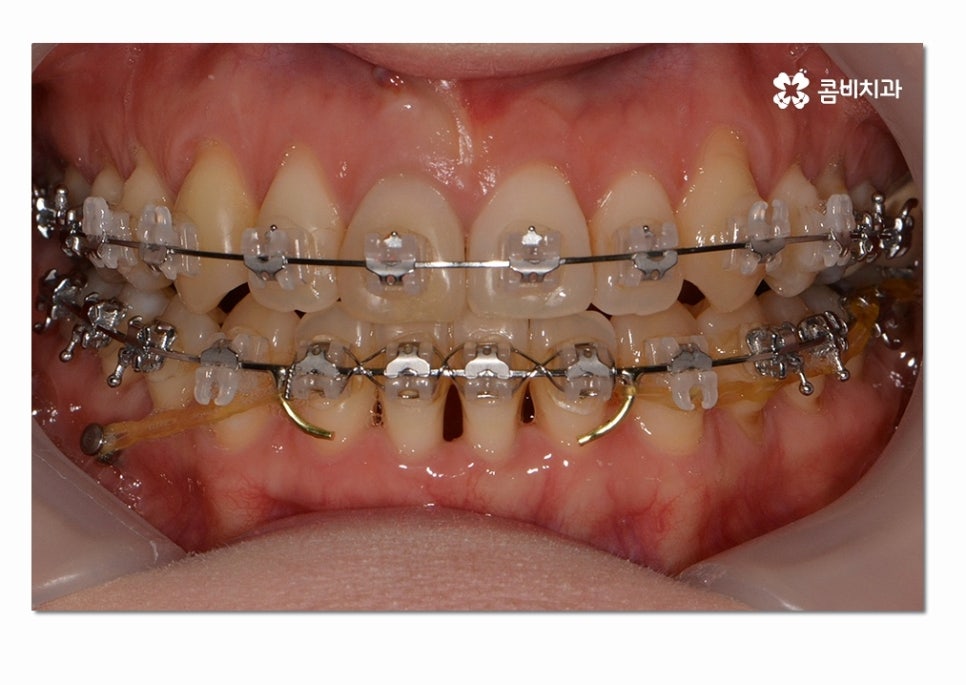

치료 경과에 따라서 윗니가 아랫니를 덥게 되는 정상적인

교합 상태로 치열이 변화하는 것을 보실 수 있는데요.

치아교정을 원하신다면 겉으로 보이는 치열 상대가 가지런한 것도

중요하겠지만 오늘 설명드린 것처럼 교합이 무척이나 중요하며

치열이 변화하면서 자신의 얼굴과 자연스럽게 잘 어울리는지

얼굴 변화와 조화에 대해서도 철저하게 따져봐야 할 거예요.